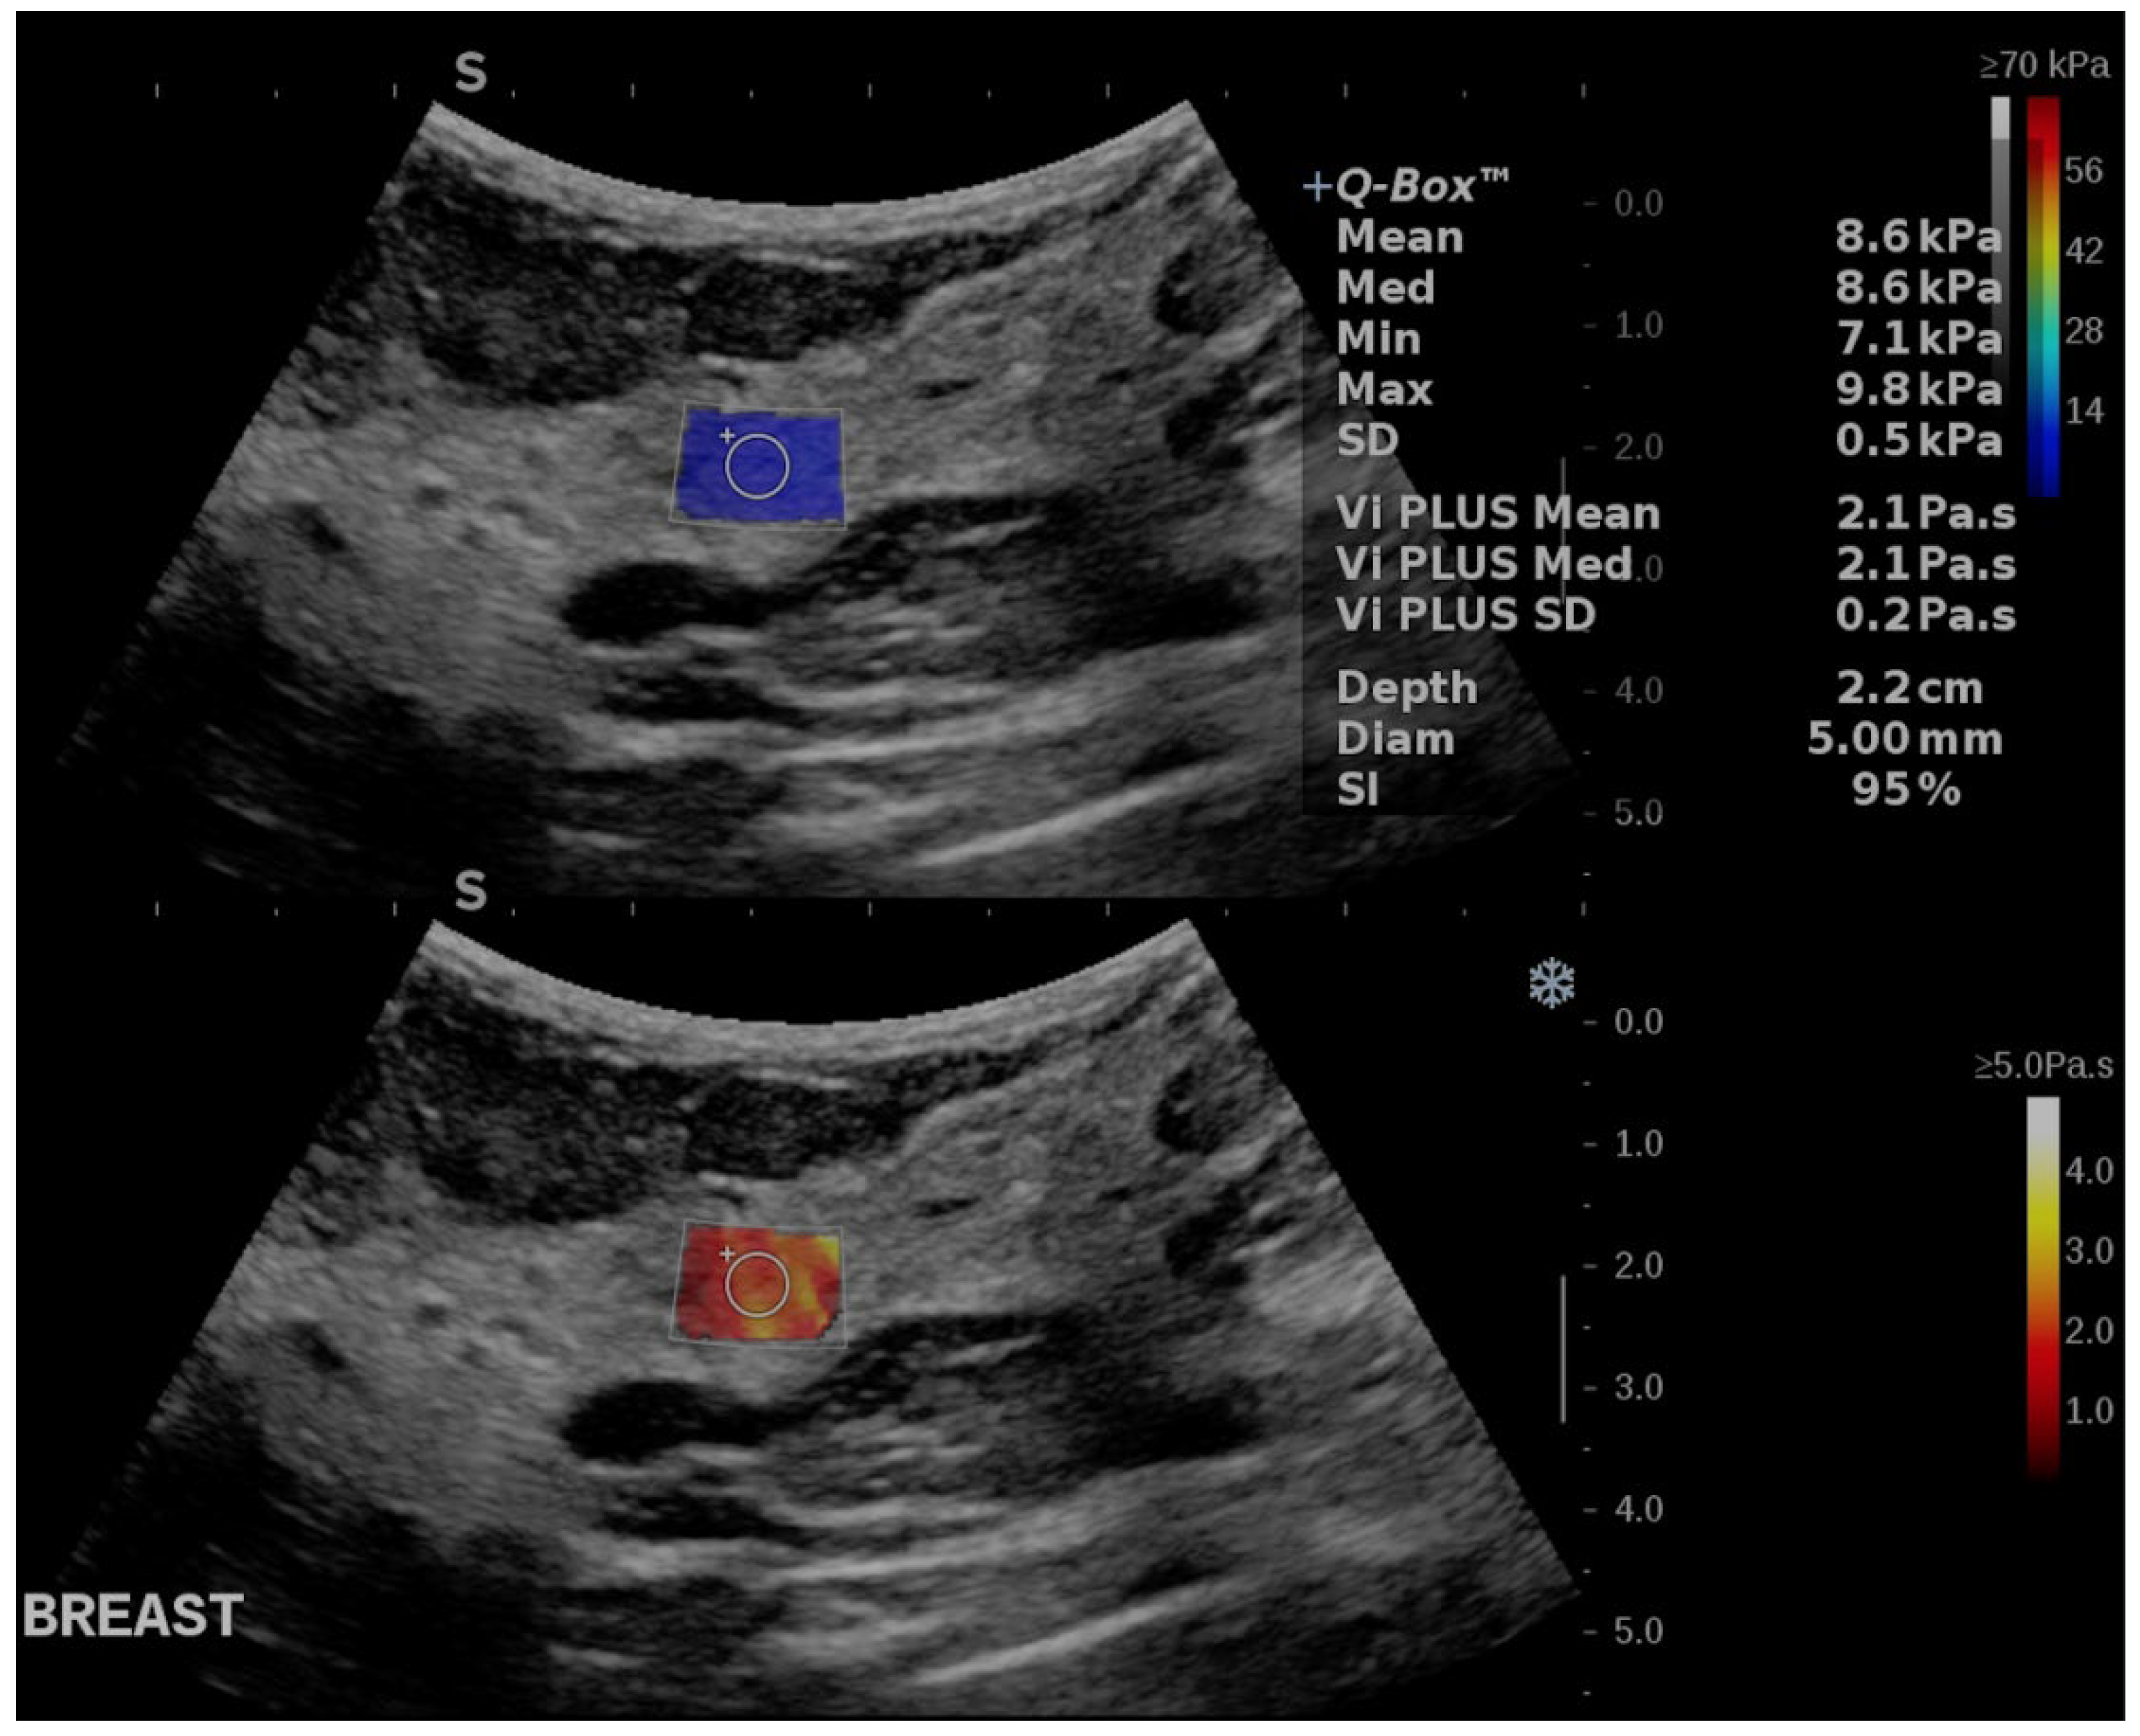

2.2. Ultrasound Acquisition Technique